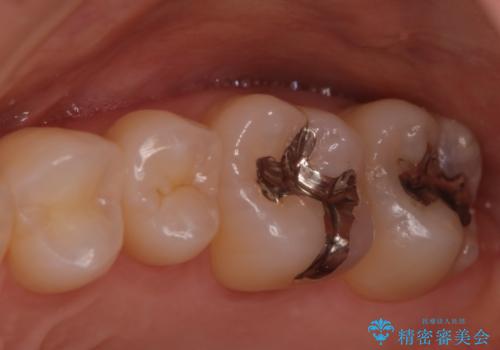

- 奥歯の銀歯が目立つということで来院されました。もともと入っていた銀歯を取り、虫歯の治療を行い、型取りを行ないます。

よく銀歯の下が虫歯になっていることがあります。

今回の患者様も銀歯を取ってみたら大きな虫歯になっていました。